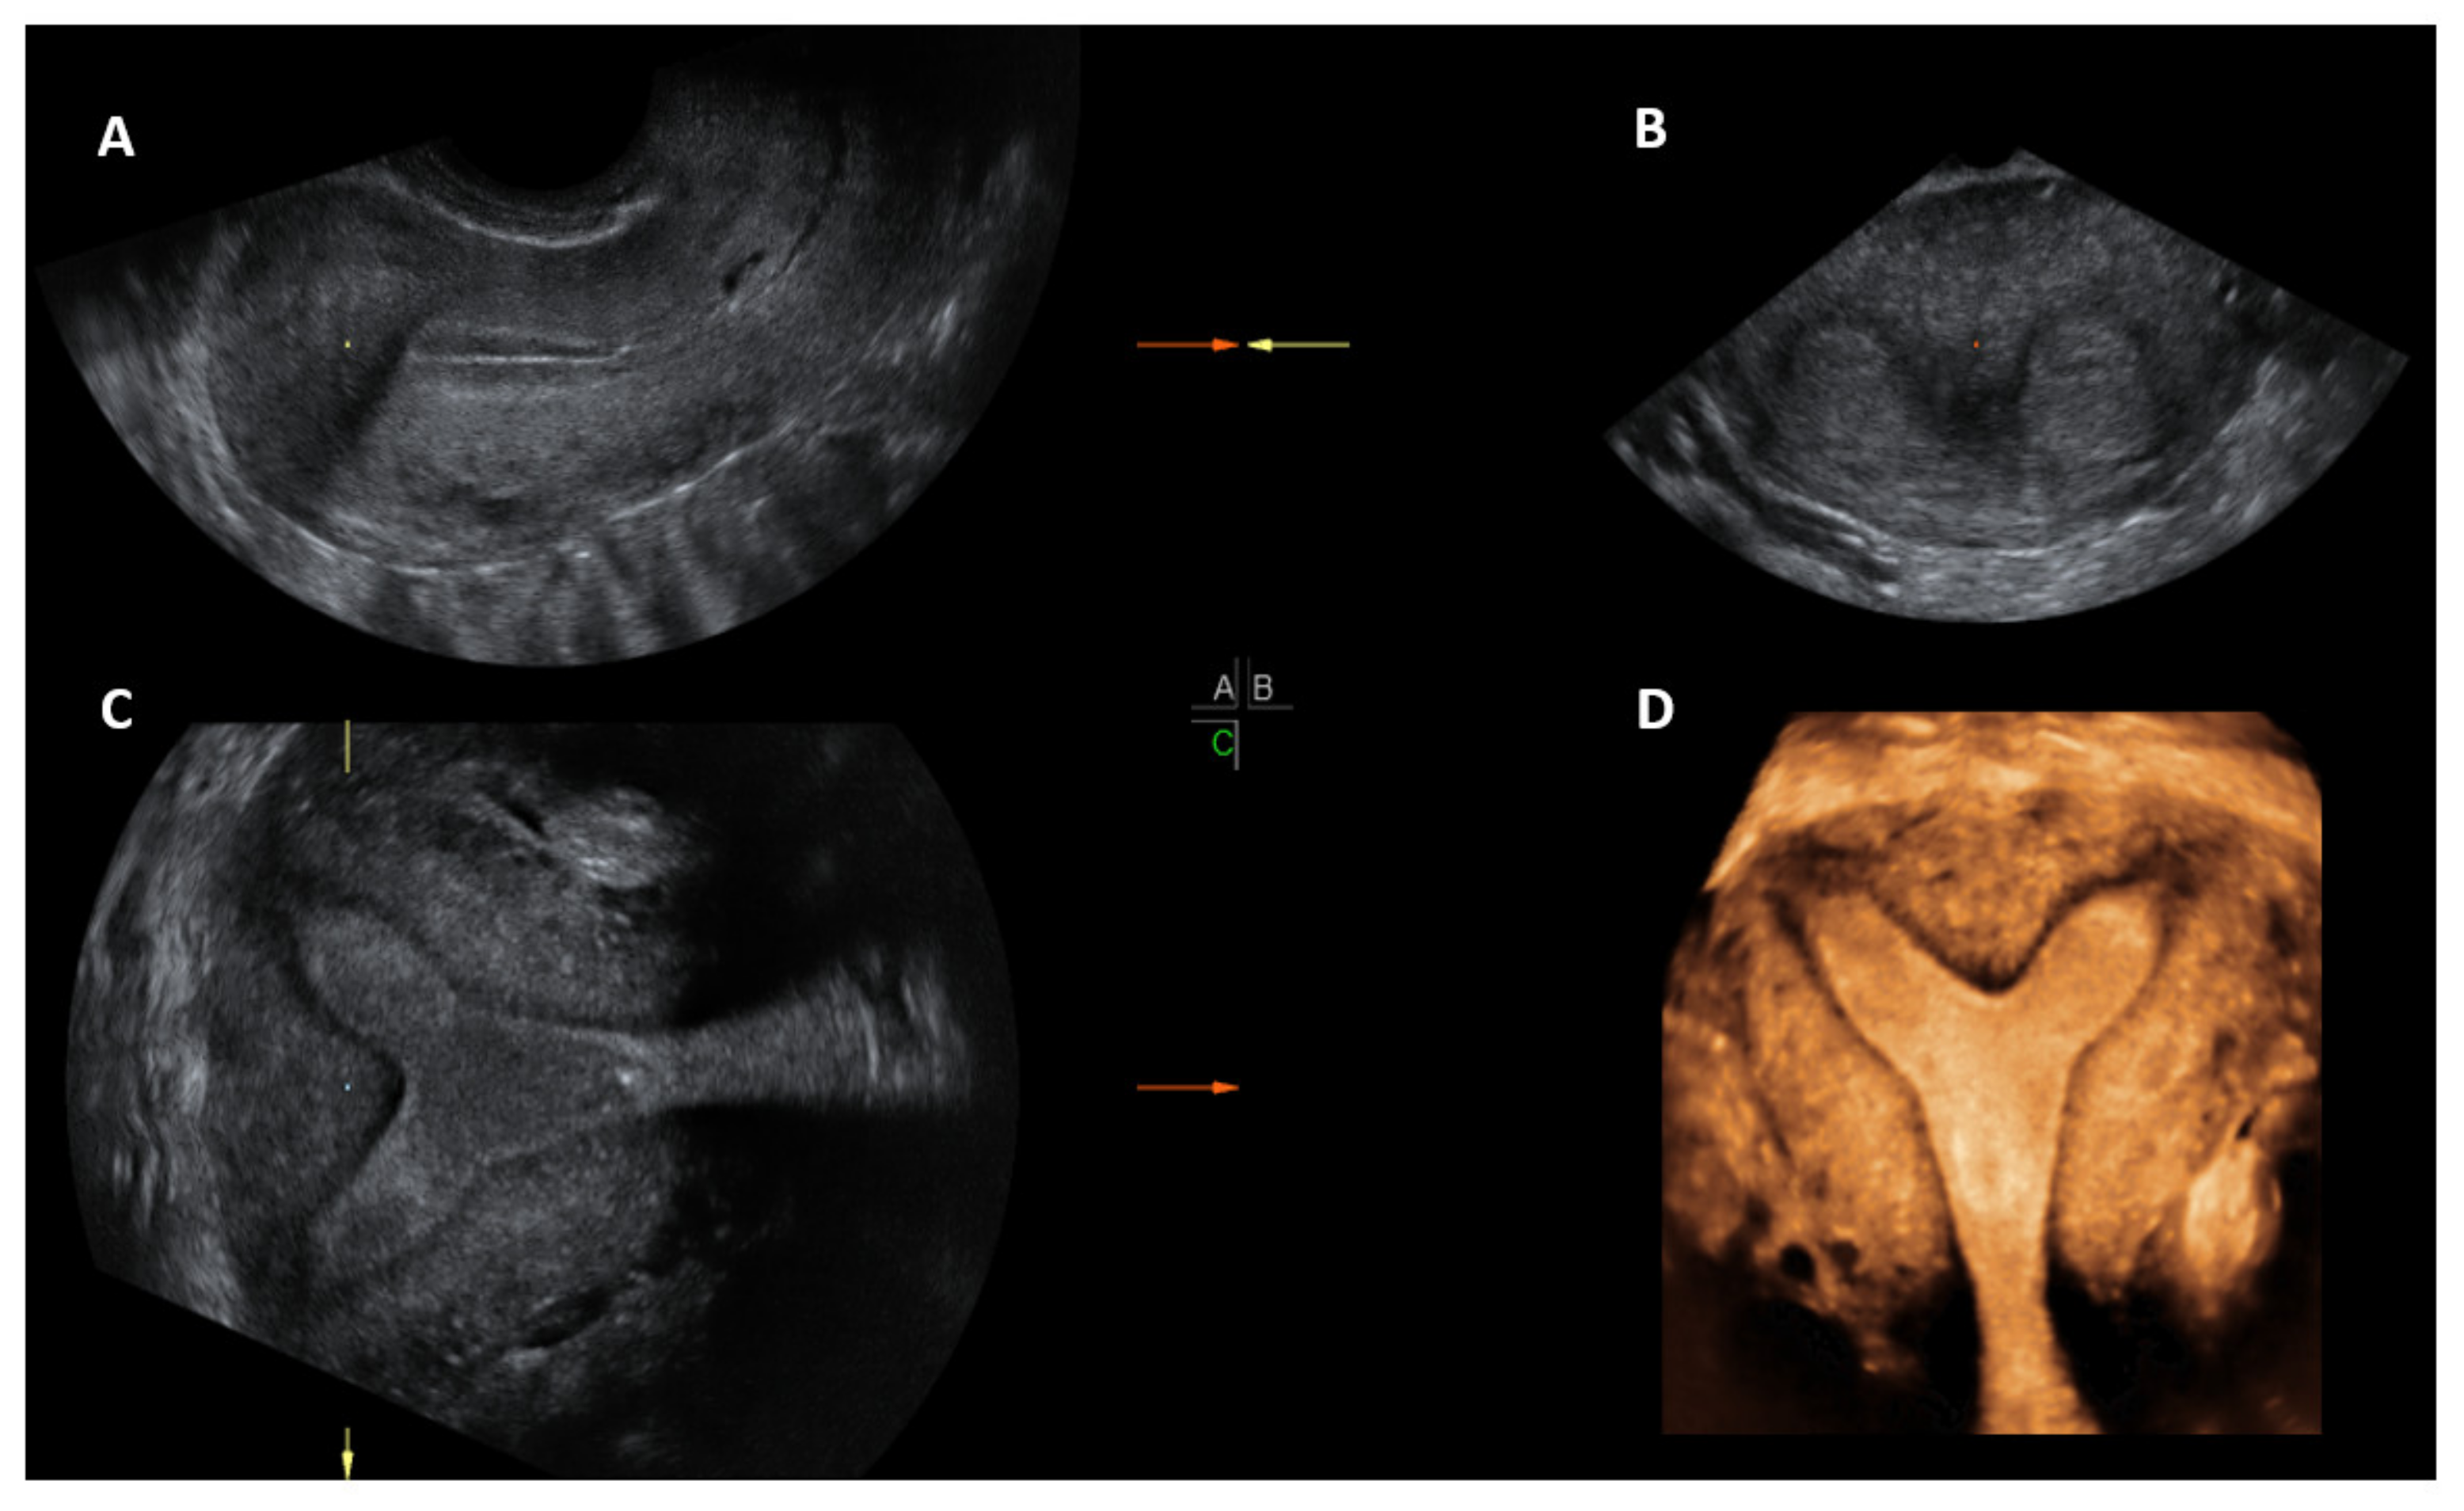

Once the 3D acquisition is completed, the uterus is displayed on the screen in three orthogonal planes (A, B, C), which can be viewed in various different modes according to the US machine used (Figure 6 and Figure 7). The default display is in the sectional mode and the operator can choose the render mode, which enhances the contrast between the two areas by recreating an impression of depth and improves visual perception. The operators should familiarise themselves with manipulation of the uterus in the three planes using the X, Y and Z functions on the US console.

When the render mode is selected, a region of interest (ROI) box will appear on the screen. The ROI box should be manipulated so that it covers the endometrial cavity in its entirety. The green line of the ROI box indicates the direction of rendering and this should ideally be placed on top. Final adjustments can be made, such as curving the ROI box, along the curvature of the endometrial cavity and applying different render options, including Omniview, Volume Contrast Imaging (VCI) and HD live, which produces a more realistic image. Once the operator is satisfied with the 3D image, this can be enlarged and can correctly classify the type of CUA. The entire volume and individual image can be saved for later analysis. [18]. The post-processing of the stored image can be performed as described above on the ultrasound machine itself (commonly done) or using ‘4D view’ software in a computer (Figure 5).

Figure 6. 3D ultrasound scan of a subseptate uterus showing simultaneous display of longitudinal plane (A), transverse plane showing two endometrial echoes (B), coronal plane (C), unique for 3D ultrasound and Rendered view of coronal plane demonstrating subseptate uterus (D).

Figure 7. 3D multiplanar view with rendering box using 4D view software: Green line of the rendering box placed on top and at the level of endometrial cavity in the longitudinal plane (A); transverse plane (B), Coronal plane (C) and rendered coronal view of uterus in the bottom right corner (D).